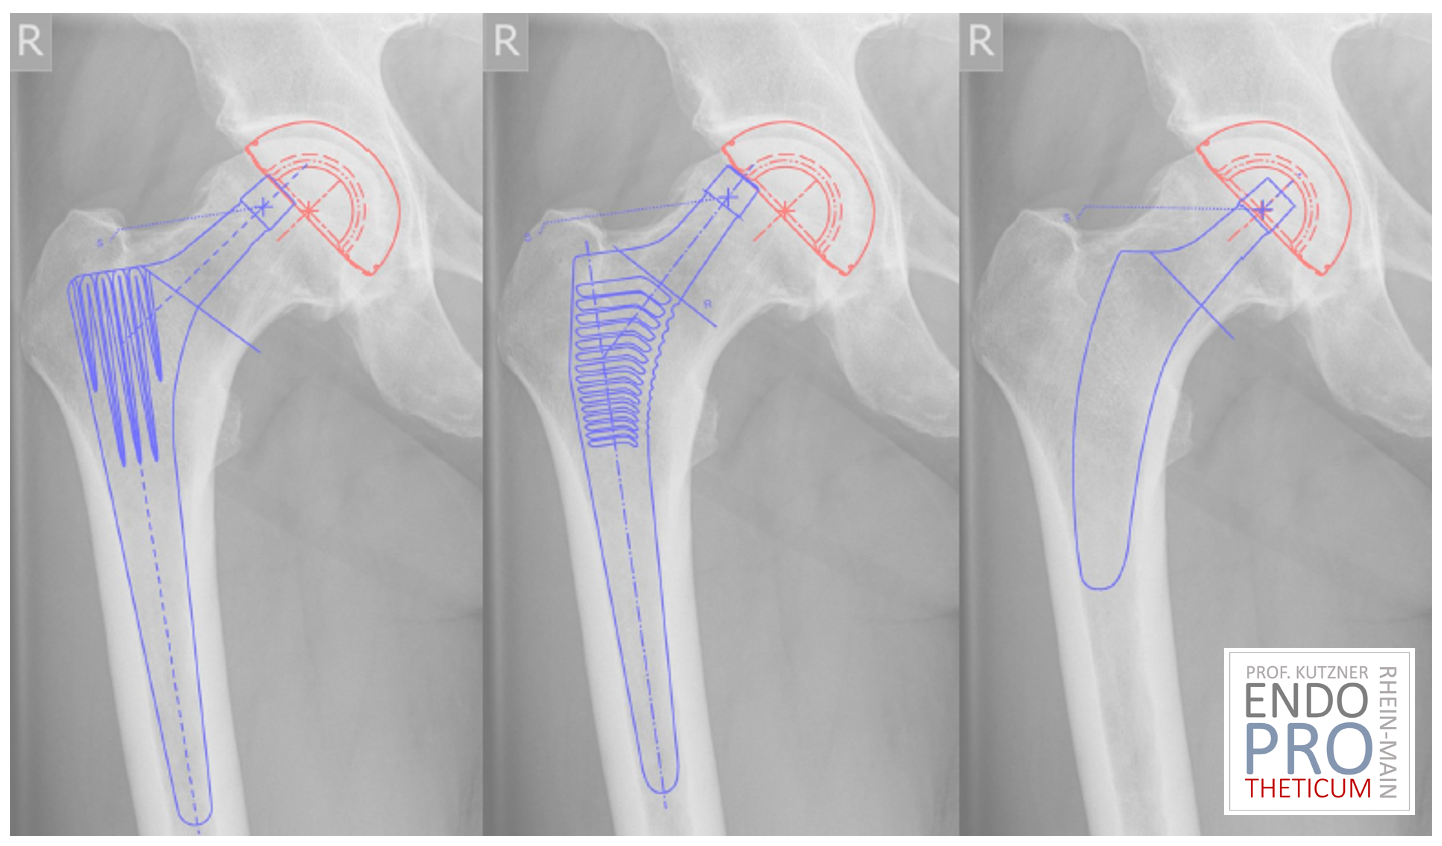

- präzise Planung

- Verständnis der Anatomie

- Erfahrung mit metaphysärer Fixation

Im Gegensatz zum Standardschaft ist die Positionierung weniger tolerant gegenüber Fehlern.

Deshalb ist die Spezialisierung entscheidend.